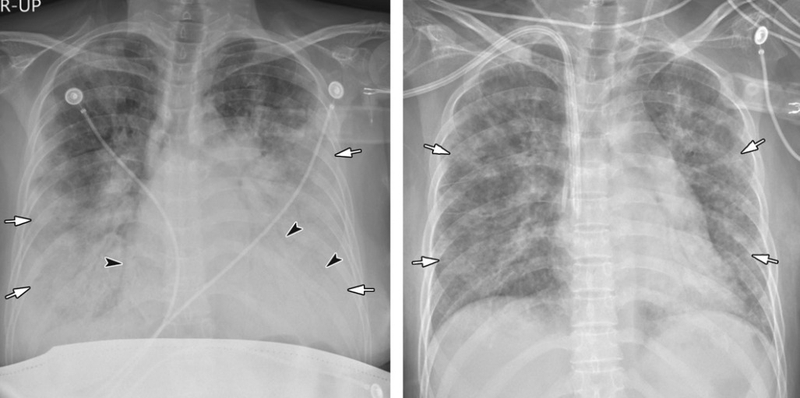

Chụp X quang viêm phổi ngoài sử dụng để đánh giá tình trạng phổi thì phương pháp này cũng cho phép đánh giá bóng tim, mạch máu và cấu trúc xương sườn của người bệnh để đưa ra chẩn đoán và xác định các tình trạng sau:

Dưới hình ảnh chụp X quang viêm phổi, bác sĩ có thể phát hiện và xác định một số bệnh liên quan đến phổi và các tạng gần đó: